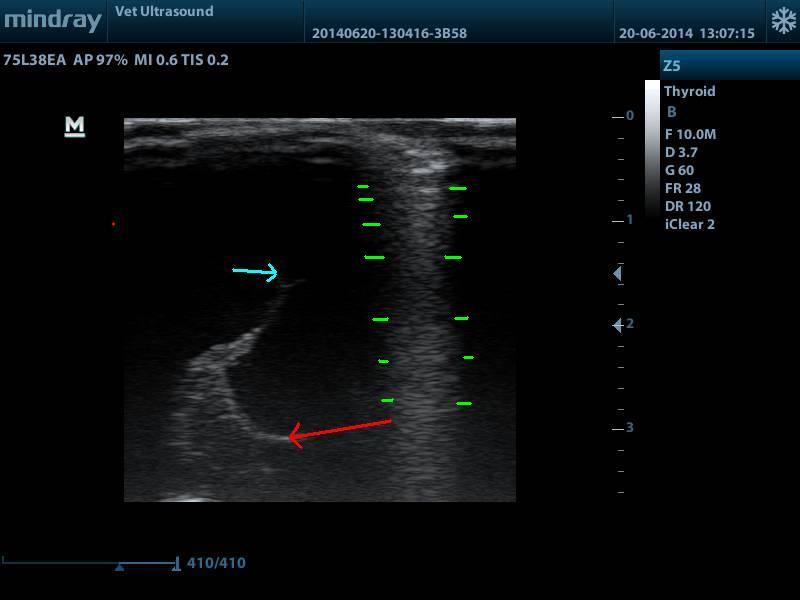

ΣΤΗΝ ΕΙΚΟΝΑ ΑΥΤΗ ΒΛΕΠΟΥΜΕ ΤΗΝ ΔΙΑΤΑΣΗ ΤΗΣ 3ΗΣ ΚΟΙΛΙΑΣ ( ΜΠΛΕ ΒΕΛΟΣ ), ΔΙΕΝΓΚΕΦΑΛΟΣ ( ΚΟΚΚΙΝΟ ΒΕΛΟΣ ), ΟΙ ΠΑΥΛΕΣ ΑΦΟΡΙΖΟΥΝ ΤΟ REVERBERATION ARTIFACT ΠΟΥ ΔΗΜΙΟΥΡΓΕΙΤΑΙ ΛΟΓΩ ΜΗ ΚΑΛΗΣ ΕΠΑΦΗΣ ΤΟΥ ΗΧΟΒΟΛΕΑ ΜΕ ΤΟΝ ΑΣΘΕΝΗ.